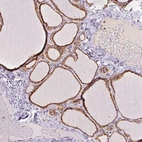

Immunohistochemistry analysis in human thyroid gland and skeletal muscle tissues using Anti-PRKCSH antibody. Corresponding PRKCSH RNA-seq data are presented for the same tissues.